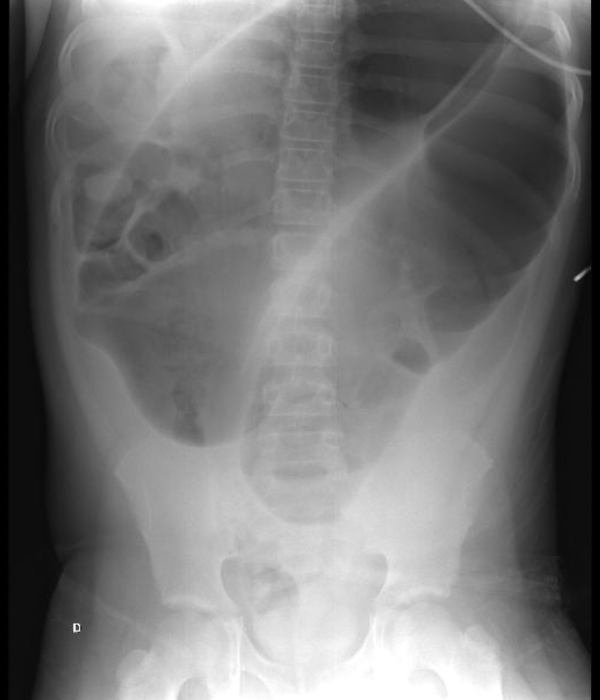

Sigmoid volvulus

Coffee bean sign

Cecal volvulus